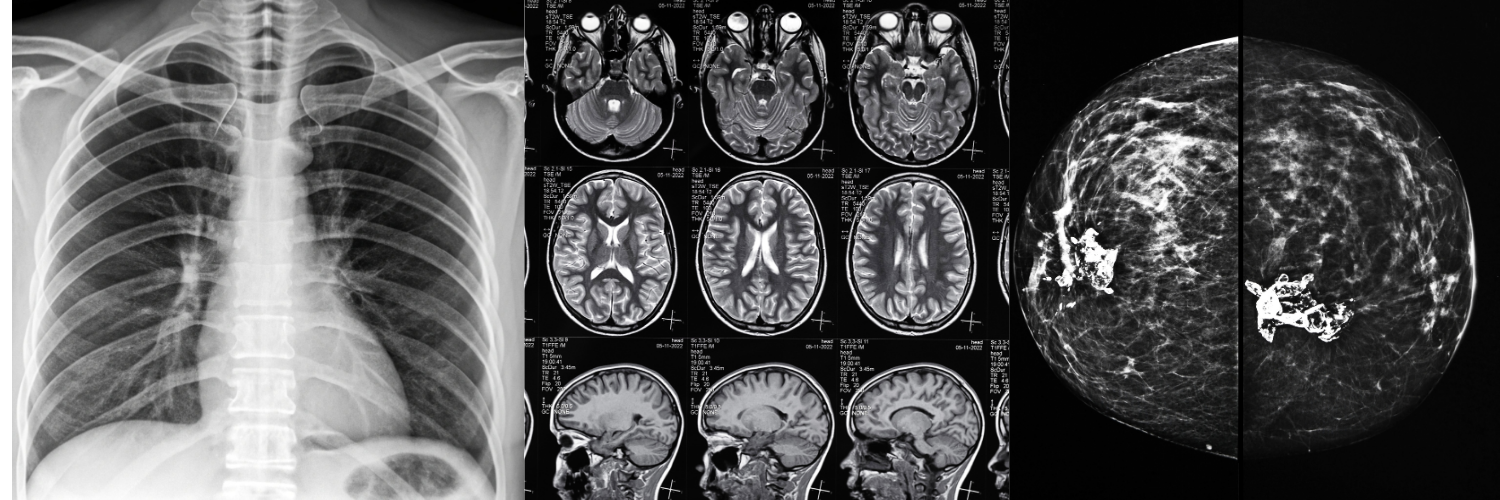

TELERADIOLOGY AND SECOND OPINION SERVICE

We can review your radiological studies and provide you with a second opinion from various subspecialists in different areas of radiology.